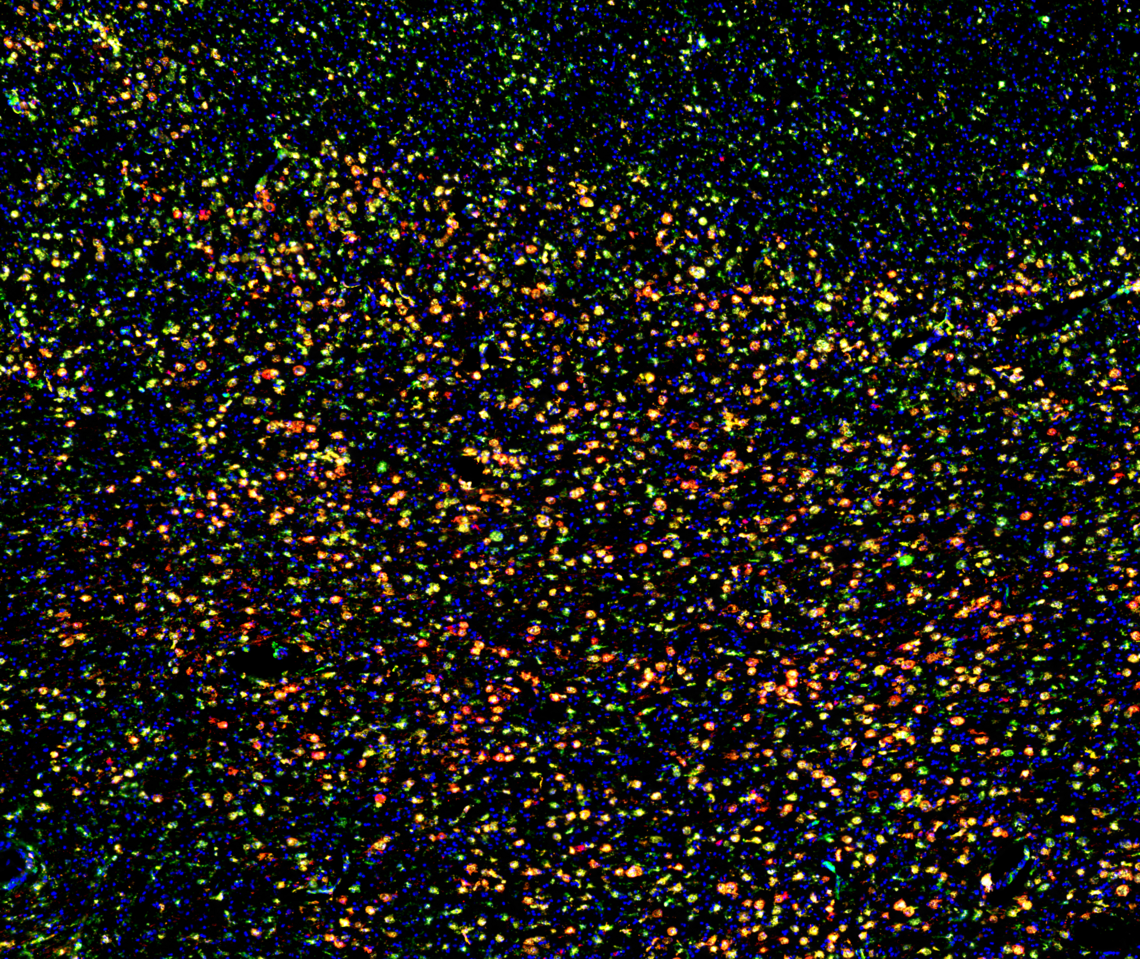

Plasma cells (CD138) localized in the subcapsular sinus (CD31) lined with macrophage (Iba1). B cell follicle filled with B cells (B220) that are primarily naive (IgD). T cell zone tilled with CD4+ T cell (CD4) and dendritic cells (MHC-II).

Identifying pathogenic B cell subsets and their mechanisms in MS lesions

B cells can promote and suppress the progression of MS but we currently do not know which subsets of B cells exist in the brain, their locations in the brain, or the mechanisms that B cells are using to modulate MS progression. In my project, I will address these problems by fully characterizing the locations and subsets of B cells in MS lesions. Using an animal model and cells in culture, I will identify the major mechanism(s) that B cells are using to promote or suppress CNS damage and determine whether cellular interactions in MS lesions influence B cell pathogenesis.